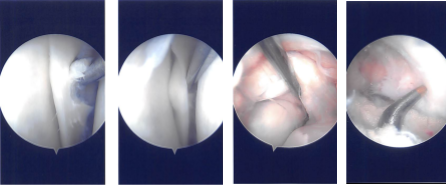

Intraoperative Arthroscopy Images

The intercondylar area was examined and the acromioclavicular ligament was found to be intact. The lateral femoral condyle was examined, and the lateral meniscus was intact. There was no cartilage damage on the lateral femoral condyle.

Now the repair of the bucket-handle tear of the posterior horn of the medial meniscus was started using FasT-Fix. Four FasT-Fix were used and taking bite, the peripheral and then the central part of the meniscus was performed.

The suture was cinched and tightened to find the good reduction of the tear. The tear was opposed well after the use of the four FasT-Fix. The chondroplasty of the patella was also done. The knee was irrigated and washed.

Intraoperative Arthroscopy Images

The scope was moved to the intercondylar area where ACL was found to be intact. Partial synovectomy was performed in that region. The scope was moved to the lateral femorotibial compartment where the left meniscus was intact. no chondral damage to the lateral femoral condyle.

Then, the scope was reentered into the patellofemoral joint where the trochlea was found to have grade 1 condylar lesions. No chondroplasty was performed on the trochlea. There were grade 2 to grade 4 lesions on the inferomedial patella facet. Chondroplasty was performed.

Now, the scope was moved from the lateral to the medial working portal. The lateral working portal was clean and using a shaver to make easy access to the medial meniscus.

Zone specific cannulas were reused to pass sutures through the medial posterior horn and body of the medial meniscus through the capsule. Three horizontal and one vertical mattress suture were used. They were held firmly and found to have made a good reduction of the meniscus